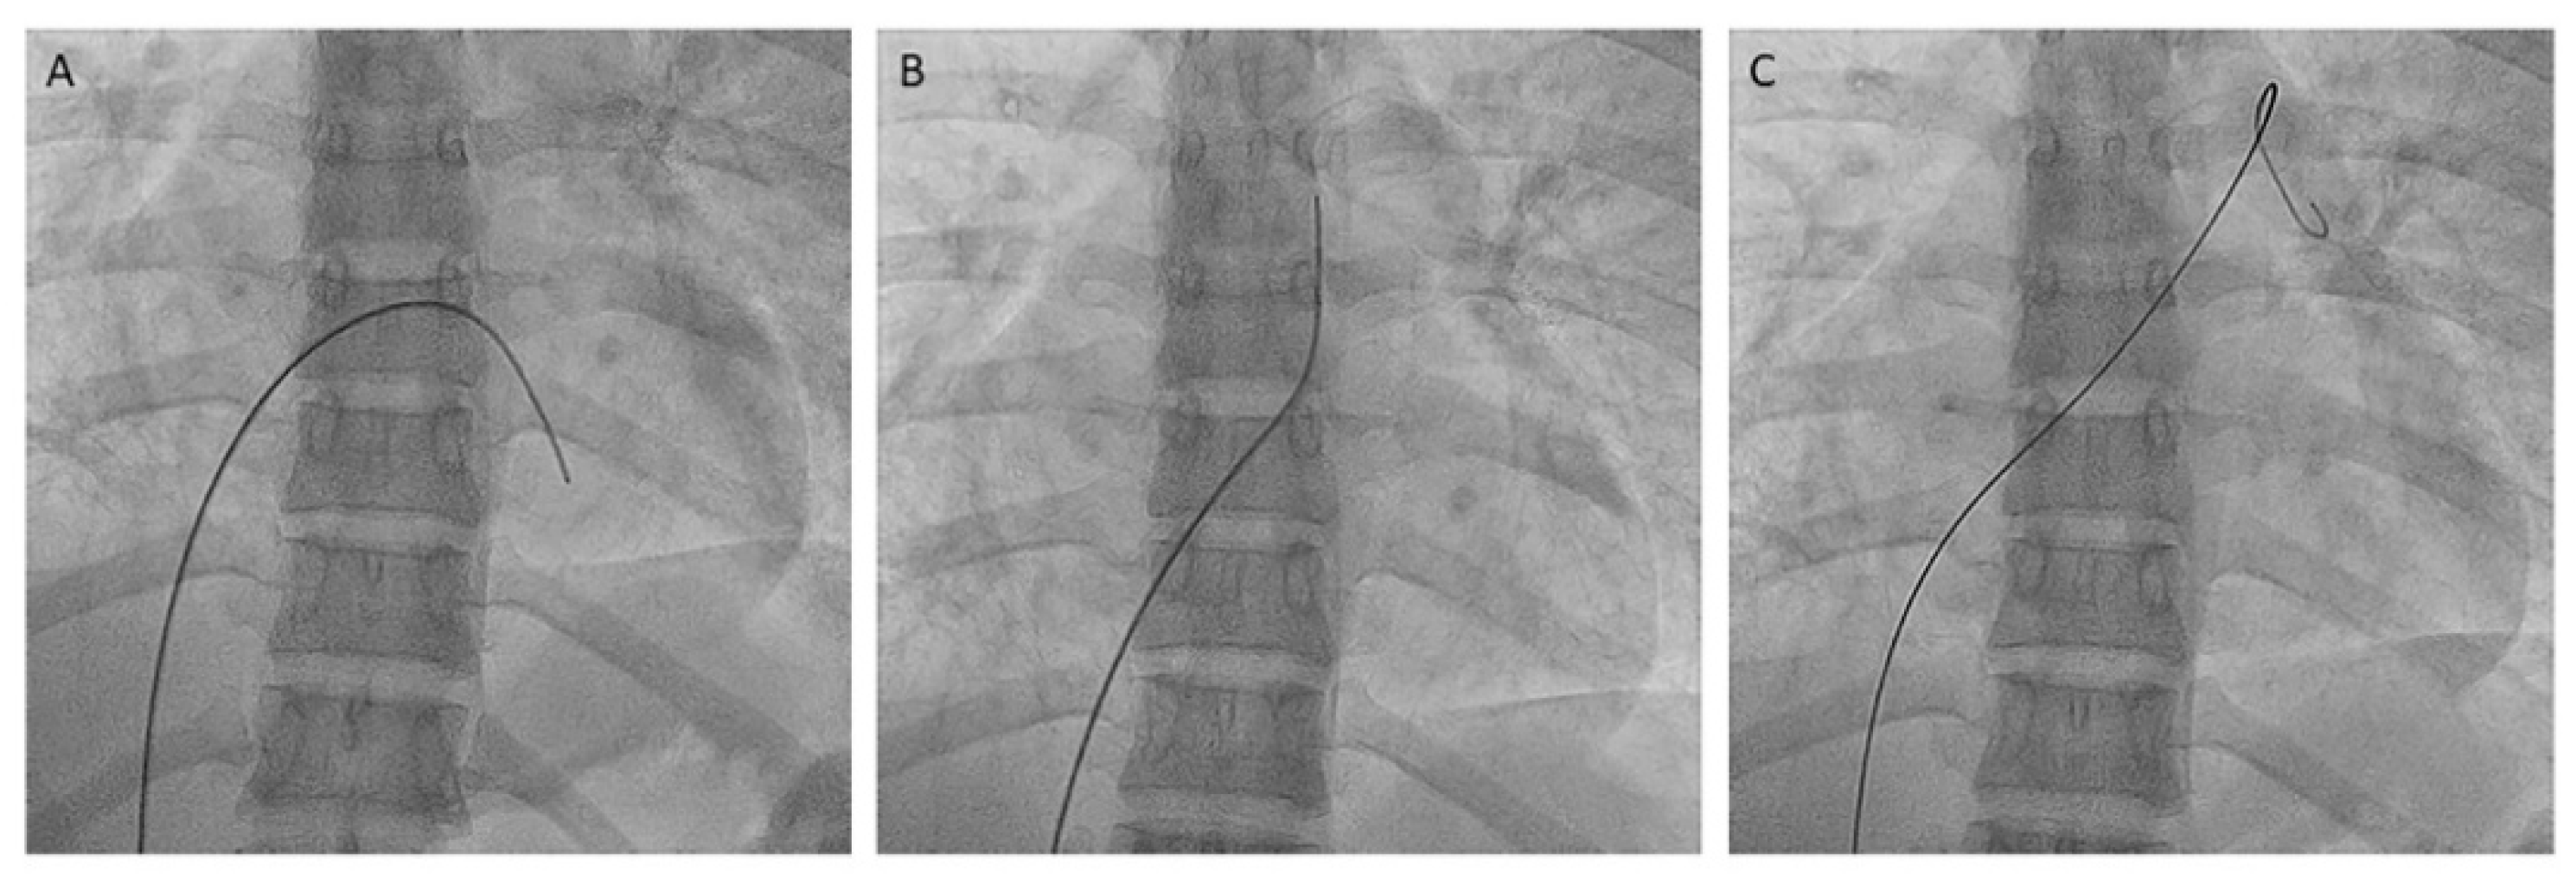

- Left upper lobe. The apico-posterior trunk (A1/2) is easily cannulated in the AP view. We should rotate the MP-A2 catheter counterclockwise in the proximal segment of the LPA to make the tip face upwards (Figure 23). The apical and posterior segmental arteries (A1 and A2) are well visualized by filming in the AP and lateral views. The anterior segmental artery (A3) is engaged more easily with the Judkins left catheter (JL) 3.5 or 4. Position the JL below the aortic arc in the AP view with the distal tip facing the left lateral chest wall. Rotate the catheter counterclockwise and withdraw it slightly. The distal tip of the catheter will climb 2–3 cm, engaging the anterior segmental branch (A3) (Figure 24). Film this branch in the cranial RAO and lateral views.

- Lingula. The lingula artery is easily cannulated in the AP view with the JL 3.5/4 catheter (depending on the PA dilatation). The maneuver and position in the AP view is the same as described for the anterior segmental artery of the left upper lobe (A3), though somewhat lower (Figure 25). Amplatz left 1 or 2 is also a good choice for catheterization of the lingula branches. In addition, this catheter gives extra support when performing BPA of these branches. The two lingula segmental arteries are well displayed in the lateral and in the cranial RAO/cranial AP views.

- Left lower lobe. The two trunks of the basal pyramid and the superior segmental artery (A6) are easily cannulated with the MP-A2 in the lateral projection (Figure 26). The anterolateral trunk (A8/9) sometimes requires the Judkins right (JR) 4 or the JL 3.5/4. We should sequentially film both trunks and the superior segmental artery (A6) in the lateral and AP view.